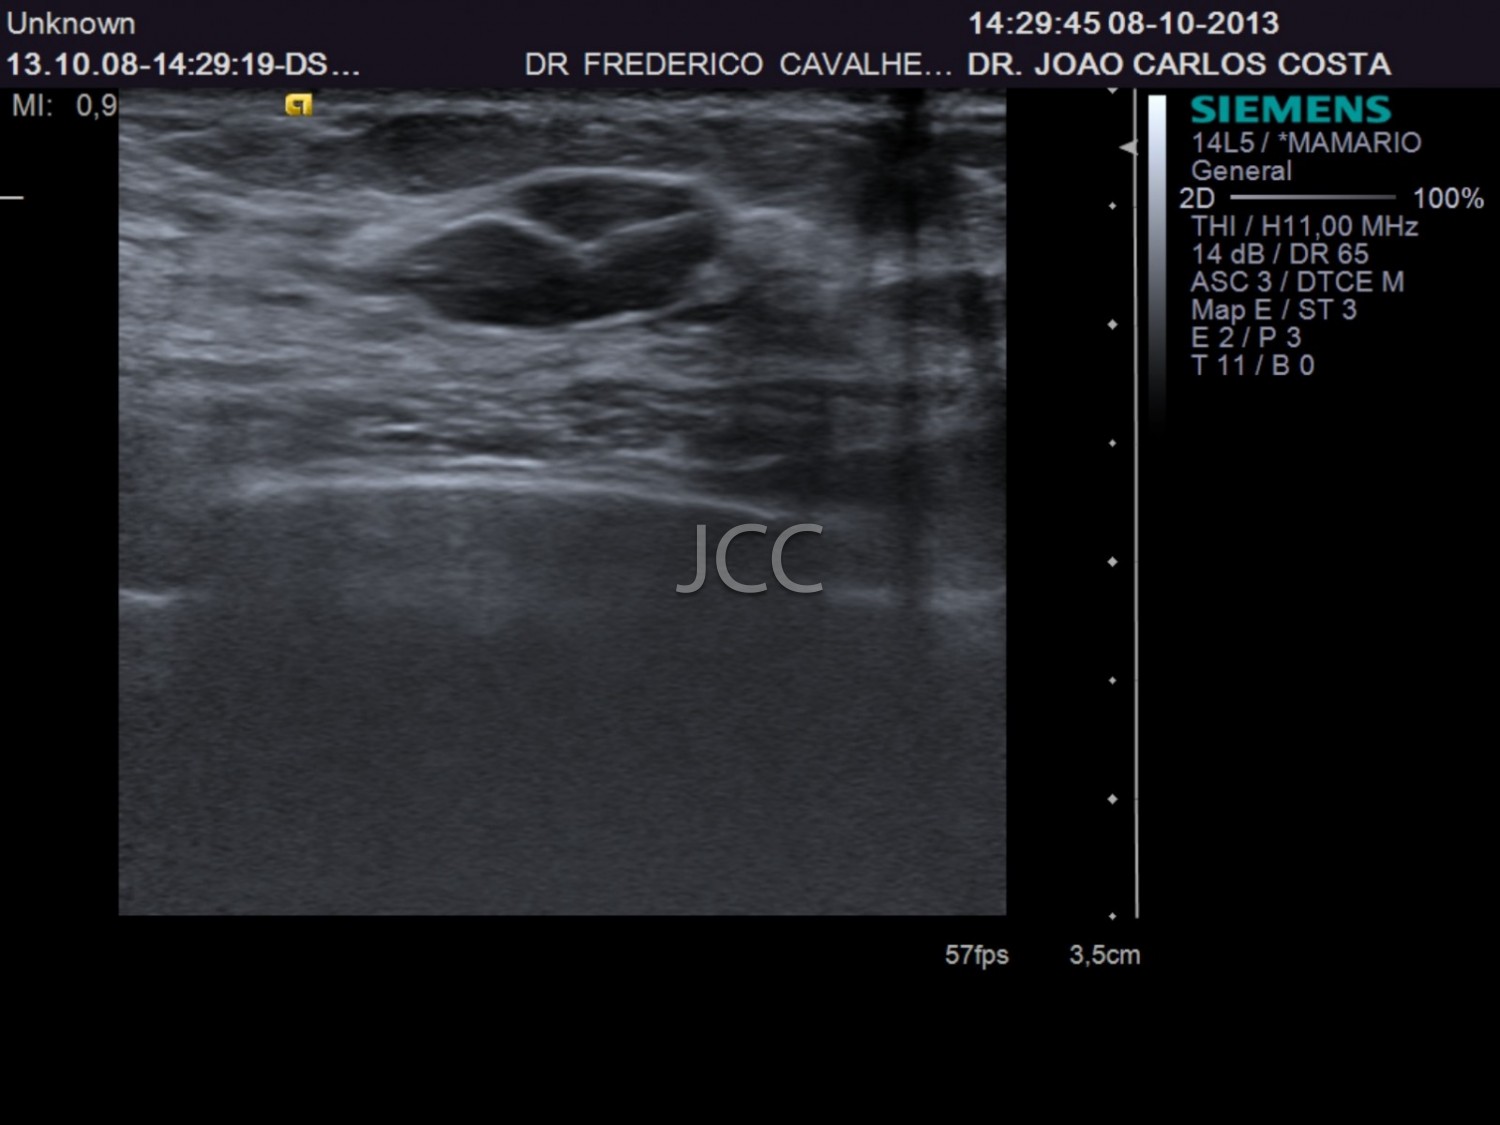

Ecografia - Biópsia por ecografia

A Ecografia constitui um método mais acessível permitindo de modo simples e rápido a avaliação dos órgãos do corpo humano incluindo o fígado, vias biliares, vesícula, pâncreas, rins, bexiga e próstata, bem como órgãos de menores dimensões como a tiróide, parótidas e estruturas musculares.

Constitui uma óptima técnica para guiar a realização de biópsia. Quando associada ao Doppler permite o estudo das estruturas vasculares arteriais e venosas de modo dinâmico.